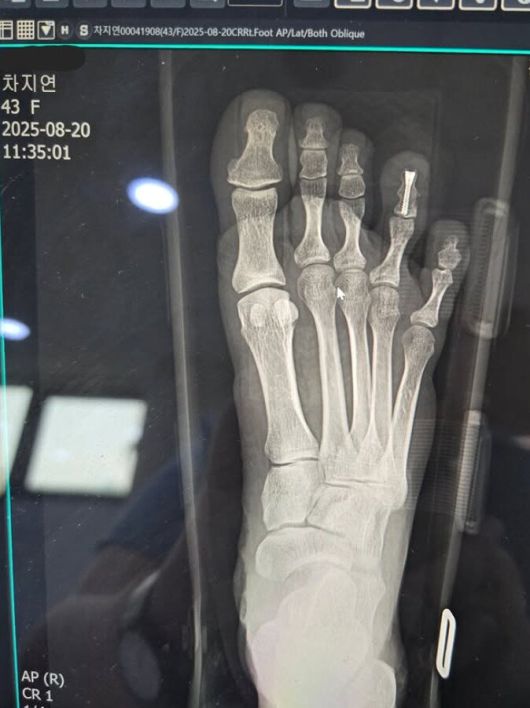

차지연은 28일 자신의 SNS(소셜미디어) 계정에 "제 소식을 들으시고 많이 놀라셨을 여러분께 먼저 죄송하다는 말씀드린다. 공연 연습 도중 오른쪽 네 번째 발가락을 심하게 부딪친 뒤 통증이 심해서 급히 응급실에 가본 결과 골절 진단을 받고 순간 심장이 덜컹했다"는 글과 함께 사진을 올렸다. 사진은 수술 후 촬영한 엑스레이로 오른쪽 네 번째 발가락에 나사가 박혀 있다.

차지연은 "오로지 공연에 대한 생각 외에는 아무것도 생각나지 않았다"며 "다음날 일찍 바로 나사를 박는 수술을 했고 오늘이 일주일이 되는 날이고 회복에 전념하고 있다"고 설명했다.